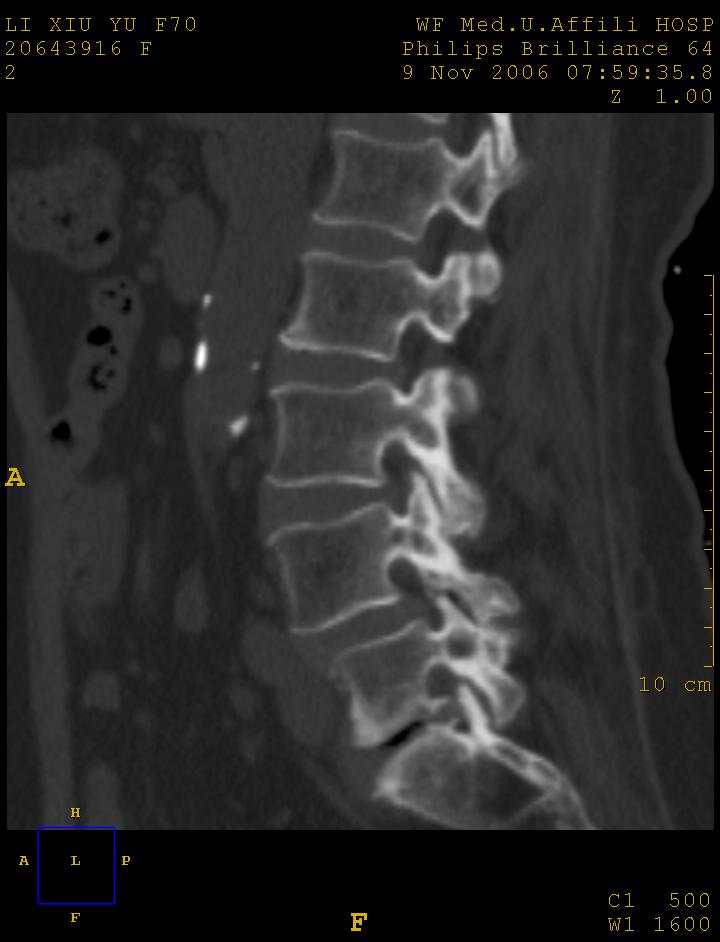

女,70岁,腰痛

l4以上向前滑脱

1腰椎骨质增生,2l4向前滑脱,3腰5-骶一椎间盘退变

l4椎体向前滑脱,椎弓裂

l3/4,l4/5,l5/s1椎间盘病变,l4以上向前ι度滑脱并椎小关节交锁、椎弓峡部断裂,椎小关节变性.

考虑:1、腰4假性前滑脱(1度,小关节退行性性骨关节病所致);

2、腰5--骶1椎间盘退行性变。

1、腰4椎体1度滑脱。2、腰椎及椎小关节退行性骨关节病。3、腰3-骶1椎间盘病变。

1:l4向前滑脱,l4-5小关节退性变。没有峡部裂。

1腰椎骨质增生,2l4向前滑脱(假性,矢状位椎弓峡部连续),3腰5-骶一椎间盘退变,4小关节面综合征